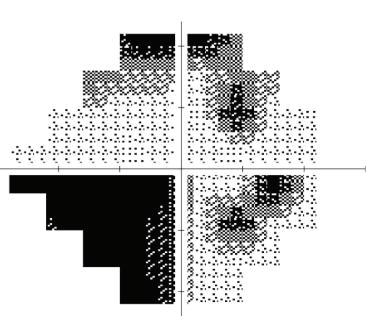

As part of our assessment, she did have optical coherence tomography of the retinal nerve fiber layer (OCTRNFL) analysis and ganglion cell complex (GCC) analysis for both eyes, which showed significant RNFL and GCC loss in the right eye more than the left. Those structural changes, corroborate with her functional changes on her visual fields where the right eye showed shows advanced visual field loss compared to milder changer in the left eye.